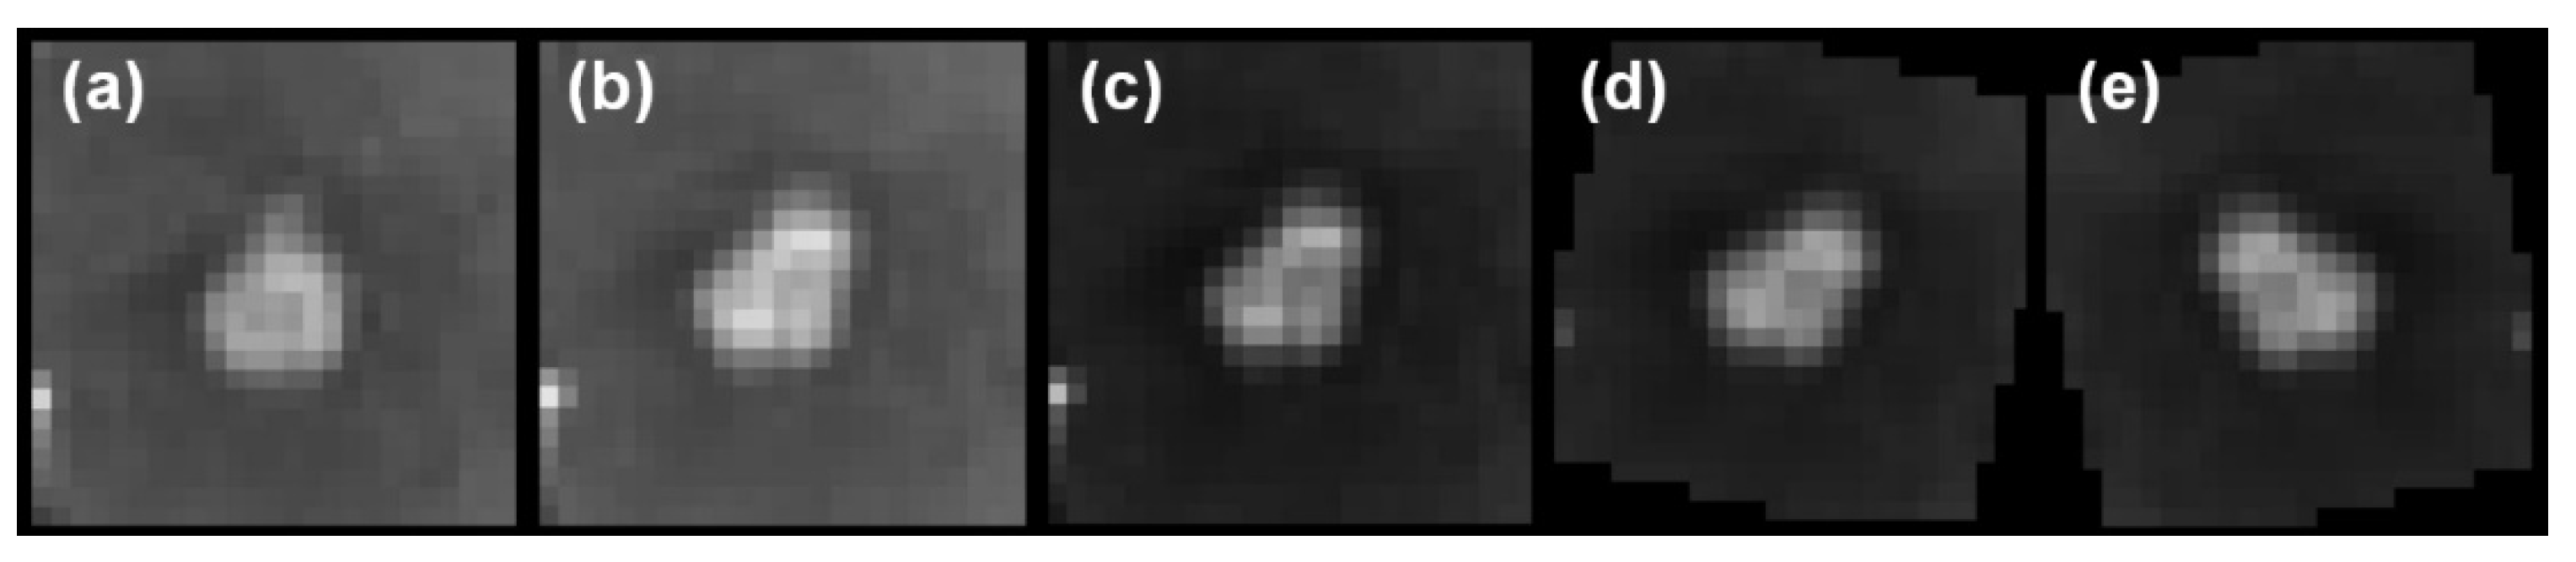

2.2. Teacher–Student Models and Noising Mechanisms